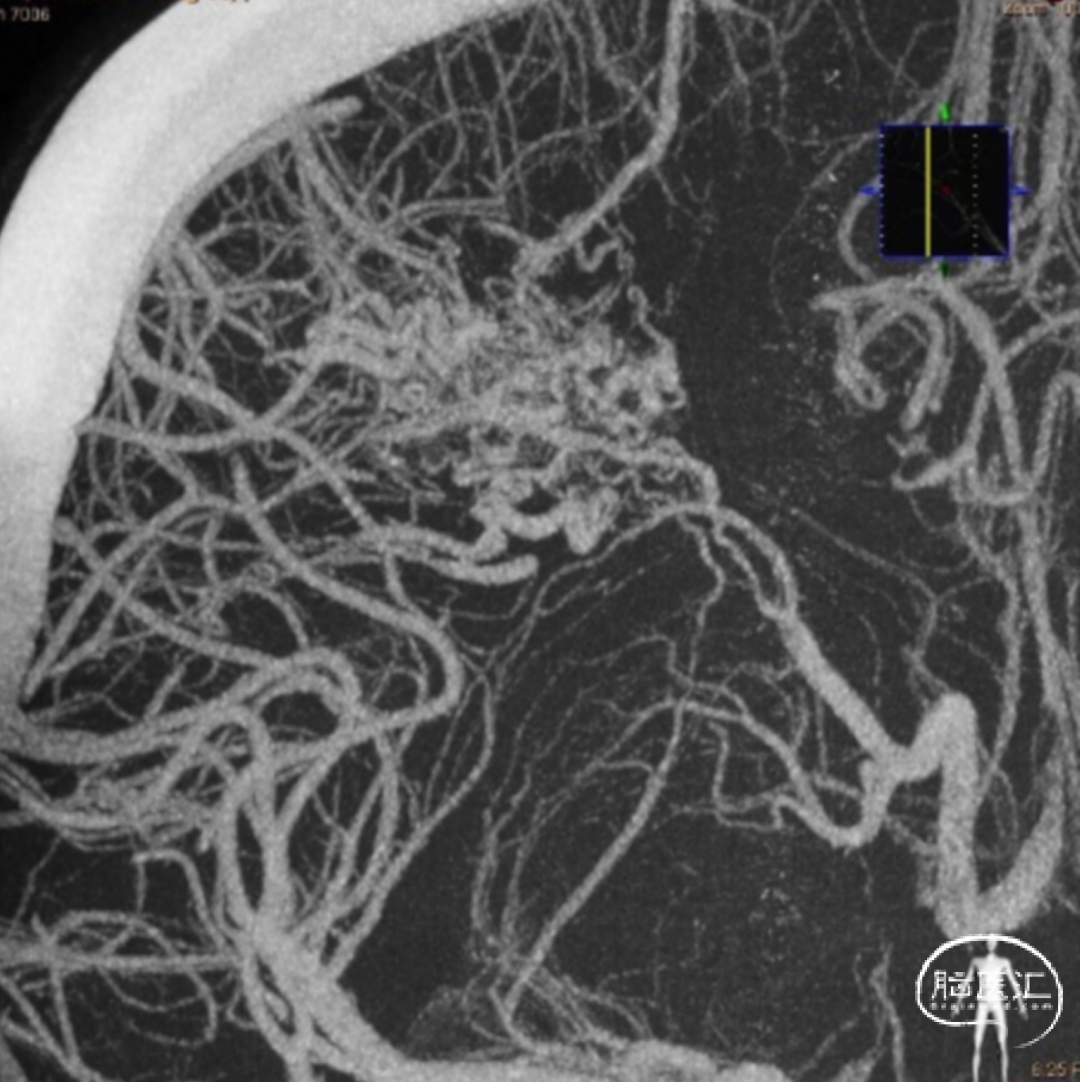

动静脉畸形(AVM):先天性脑血管变异,可能导致脑出血或癫痫发作。治疗关键在于如何精确地栓塞或切除畸形血管团,同时保护正常脑组织。

脊髓动脉瘤以及AVM的小血管高清显示,为医生提供更多信息。

脊髓动脉瘤及AVM

颅内AVM及小血管